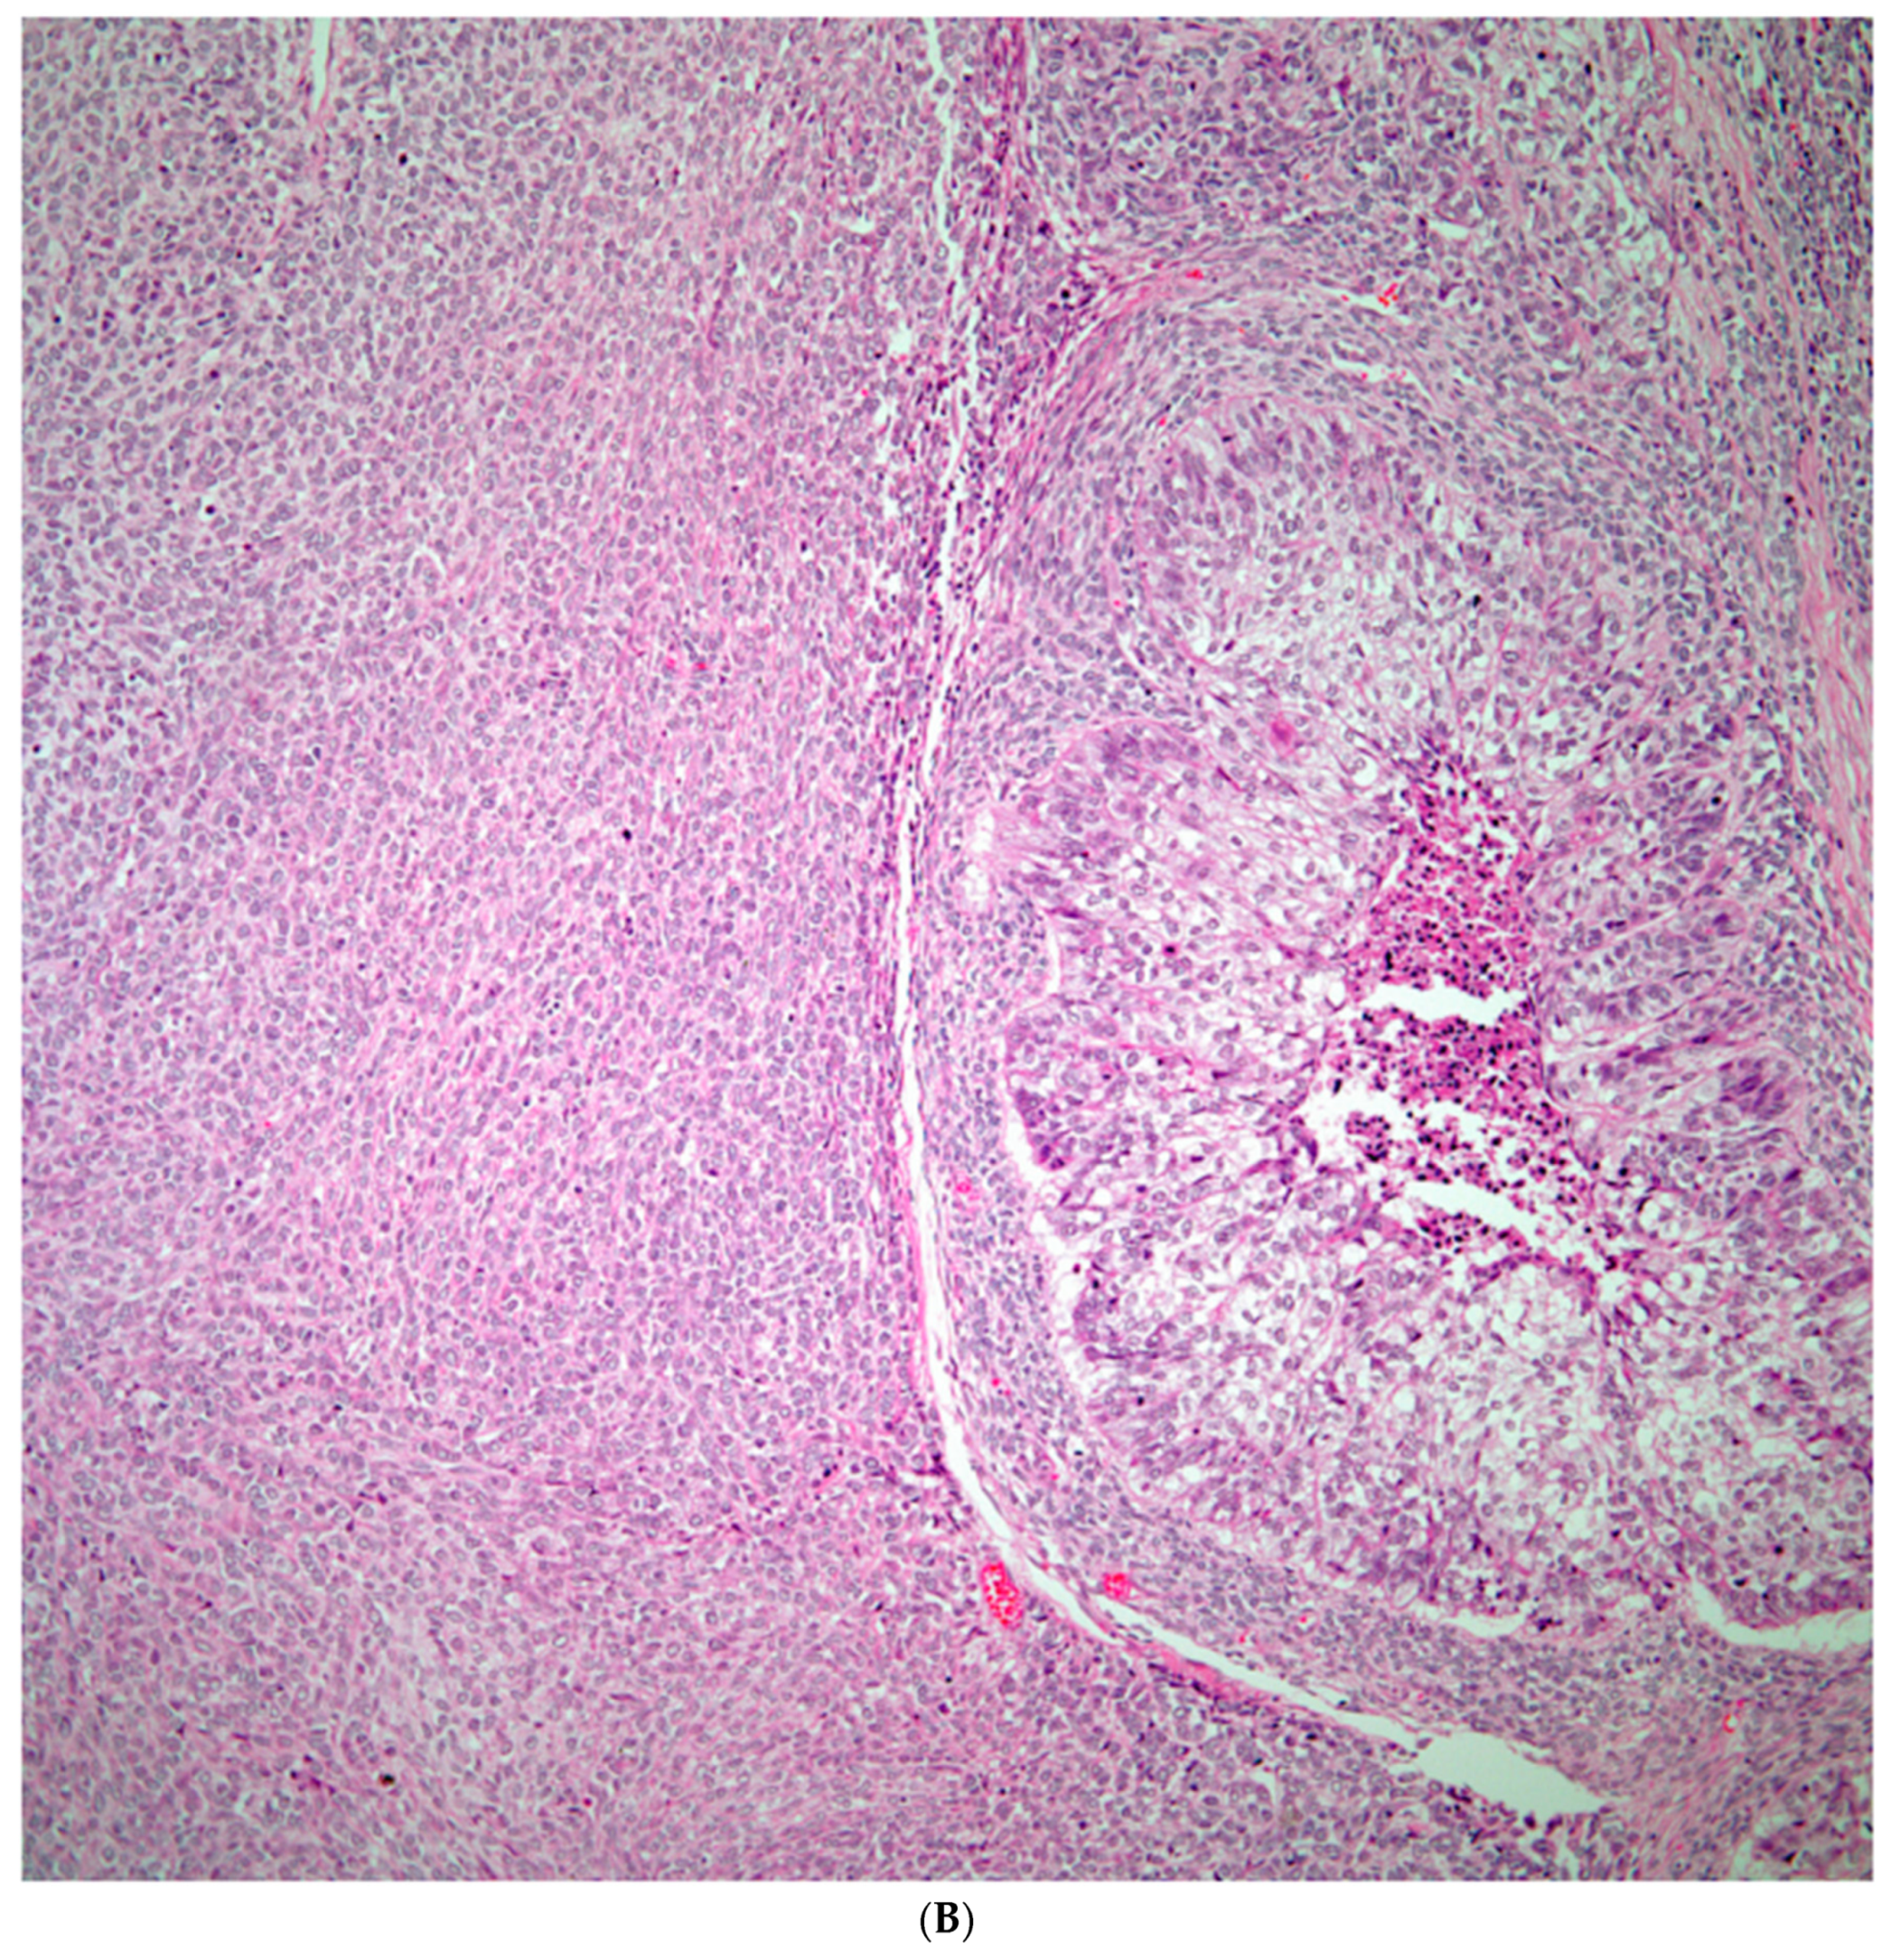

Sarcomatoid carcinomas: these tumors show a tightly packed spindle cell proliferation composed of slender cells with fusiform nuclei and inconspicuous nucleoli, replacing normal lung parenchyma. The tumors are well delimited but not encapsulated (Figure 1). Cellular atypia is variable and may show areas of mild to moderate to marked atypia. Mitotic figures also vary and may be inconspicuous or may be evident with the presence of atypical mitotic figures (Figure 2A,B). In high grade tumors, the presence of necrosis and hemorrhage is prominent and is mixed with the neoplastic component. Important to recognize is that sarcomatoid carcinomas may be associated with areas of otherwise conventional non-small cell carcinoma such as adenocarcinoma or squamous cell carcinoma (Figure 3A,B). In addition, sarcomatoid carcinoma may also show the presence of bizarre giant cells admixed with the spindle cell component (Pleomorphic carcinoma) (Figure 4).

Figure 1. Sarcomaotid carcinoma of the lung showing a well circumscribed tumor replacing lung parenchyma.